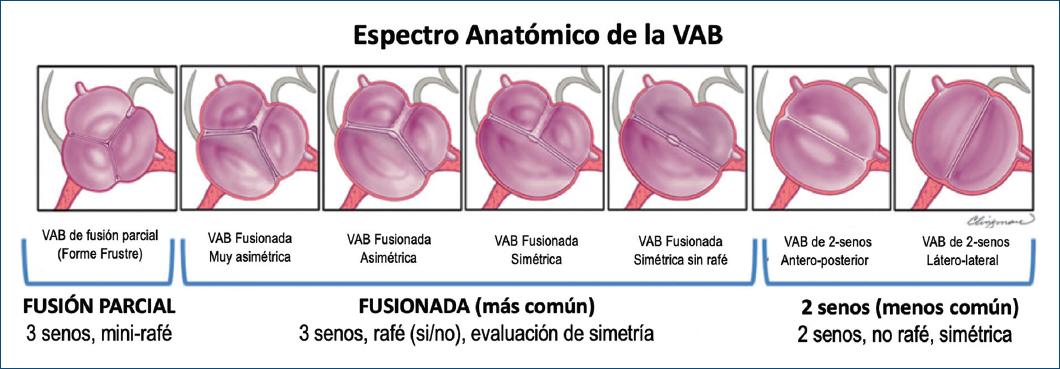

Hay tres tipos de VAB: la VAB fusionada, la VAB de dos senos y la VAB de fusión parcial, cada uno con fenotipos específicos1,6 (Fig. 4).

VÁLVULA AÓRTICA BICÚSPIDE FUSIONADA

La VAB fusionada es la más común (Figs. 5 y 6) y representa aproximadamente el 90-95% de los casos de VAB2,28. La VAB fusionada se caracteriza por dos de las tres cúspides apareciendo fusionadas o unidas dentro de tres senos aórticos distinguibles, lo que resulta en dos cúspides funcionales (una fusionada o unida y la otra no fusionada) que generalmente son diferentes en tamaño y forma (Figs. 6-8), con ángulos comisurales de la cúspide no fusionado de diversos grados (Fig. 9). Comúnmente, los pacientes con una VAB fusionada demuestran una dominancia excéntrica del seno aórtico no fusionado y su cúspide (en comparación con los otros dos senos y dos cúspides fusionados), independientemente de la edad35 (Figs. 6 y 7). Con frecuencia (aproximadamente el 70%), pero no siempre (Fig. 8), se observa una cresta fibrosa congénita entre las cúspides fusionadas, denominada «rafé»28,36. La presencia de un rafé se ha asociado con la progresión de la disfunción valvular (particularmente estenosis aórtica) y la futura cirugía valvular26,36,37. Un rafé puede estar presente pero no ser visible inicialmente en el ecocardiograma y puede hacerse visible años después38.

Hay tres fenotipos específicos de VAB dentro del tipo fusionado: fusión de cúspide derecha-izquierda, fusión de cúspide derecha-no coronariana y fusión de cúspide izquierda-no coronariana (Figs. 4, 6 y 7). El fenotipo de fusión derecha-izquierda es el más común (70-80%)2,28,39. El fenotipo de fusión derecha-izquierda es también el acompañante más común de todas las variaciones de fenotipos aórticos (aorta normal, aorta ascendente dilatada, raíz dilatada, arco dilatado) y de la disfunción valvular (insuficiencia o estenosis). Aunque este fenotipo de fusión derecha-izquierda desarrolla estadísticamente más estenosis aórtica2, se ha asociado en algunos pacientes40,41 con dilatación de la raíz aórtica, insuficiencia aórtica y preponderancia masculina (estas asociaciones se han denominado el «fenotipo de raíz»)38,39. La fusión derecha-izquierda también está fuertemente asociada con coartación aórtica en niños42.

El fenotipo de fusión derecha-no coronariana es el siguiente más común (20-30%). Se asocia con una mayor prevalencia de estenosis aórtica en adultos37 y también predice de forma independiente la progresión de la insuficiencia aórtica en adultos33. Del mismo modo, el fenotipo de fusión derecha-no coronariana se asocia con una progresión más rápida de la estenosis aórtica y la insuficiencia en niños y adolescentes42,43. El fenotipo de fusión izquierda-no coronariana es el fenotipo menos común (3-6%) en todos los estudios.

Es apropiado referirse a los fenotipos fusionados como VAB con fusión derecha-izquierda, fusión derecha-no coronariana o fusión izquierda-no coronariana. Ocasionalmente, es posible reconocer una VAB fusionada pero no poder discernir el fenotipo de fusión, en cuyo caso el término VAB con fusión indeterminada es apropiado (Fig. 4). Es importante reconocer que algunas VAB fusionadas pueden no tener un rafé congénito28 o puede tener un rafé que no es visible por medio de imágenes38, sin embargo tienen tres senos aórticos distinguibles y generalmente se pueden identificar las dos cúspides fusionadas (Fig. 8).

VÁLVULA AÓRTICA BICÚSPIDE DE DOS SENOS

La VAB de tipo dos senos es poco común, representando aproximadamente el 5-7% de los casos de VAB2,6,28. En contraste con el tipo fusionado, la apariencia de la VAB de dos senos no sugiere que dos de las tres cúspides se hayan fusionado, sino que hay dos cúspides de aproximadamente el mismo tamaño y forma, que cada una ocupa 180° de la circunferencia anular, y que estas se «formaron» dentro de dos senos aórticos solamente, lo que resultó en una válvula de dos senos/dos cúspides (Figs. 11 y 12) con ángulos comisurales de 180°. Es difícil determinar cuáles dos cúspides podrían haberse unido para formar una VAB de dos senos, pero generalmente es evidente si las cúspides son latero-laterales (de lado a lado) o antero-posteriores (adelante y atrás) dentro del plano de la base del corazón de eje corto (Figs. 11 y 12); por lo tanto, estos son los dos fenotipos específicos de la categoría de la VAB de dos senos. La VAB latero-lateral de dos senos tiene una arteria coronaria que surge de cada seno, mientras que la VAB antero-posterior puede tener una arteria coronaria que surge de cada seno o ambas arterias coronarias que surgen del seno anterior (Figs. 11 y 12). La VAB de dos senos probablemente representa una expresión más grave de los mecanismos embriológicos que conducen a la VAB fusionada. Es apropiado referirse a estos fenotipos como VAB latero-lateral de dos senos y VAB antero-posterior de dos senos. Ocasionalmente, a pesar de la sospecha, puede ser difícil estar seguro de si solo hay dos senos, en cuyo caso se pueden usar términos como posible o probable VAB de dos senos. Hay una falta de datos científicos sobre las asociaciones clínicas/pronósticas de la VAB de dos senos, que representa una forma «morfológicamente severa» de la VAB. Por lo tanto, esperamos que por medio de este sistema de nomenclatura/clasificación, la comunidad investigadora dirija más atención hacia este tipo de VAB.

LA VÁLVULA AÓRTICA BICÚSPIDE DE TIPO FUSIÓN PARCIAL (O FORME FRUSTE)

Se desconoce la prevalencia de este tipo de VAB de fusión parcial recientemente descrito (o VAB forme fruste [forma frustrada])45 (Fig. 13). La apariencia de la VAB de fusión parcial es la de una válvula aórtica tricúspide típica con tres cúspides simétricas con una apertura triangular sistólica y ángulos comisurales de 120°, sin embargo en la inspección quirúrgica o la imagen de alta resolución se observa menos del 50% de fusión entre dos cúspides en la base de una comisura, formando un pequeño «minirafé»6,45-47. Es importante reconocer y seguir estudiando la VAB de fusión parcial, que se ha descrito con mayor frecuencia en el quirófano en pacientes sometidos a cirugía por dilatación aórtica45 (Fig. 14)47. Esta VAB forme fruste resulta en la alteración de los patrones de flujo aórtico, que consiste en un aumento de la excentricidad del flujo y un aumento de los vórtices46, quizás explicando parcialmente la aparente alta prevalencia de dilatación aórtica en estos pacientes. Referirse a este fenotipo como VAB de fusión parcial o VAB forme fruste es apropiado, al igual que señalar entre qué cúspides se produce la fusión: derecha-izquierda, derecha-no coronariana y así sucesivamente.

La expresión fenotípica de la VAB representa un continuo anatómico que muy probablemente está relacionado con la severidad de sus mecanismos embriológicos. Por lo tanto, proponemos la existencia de un espectro o continuo anatómico general (Fig. 16) de los fenotipos de VAB en orden de «bicuspidización», siendo la VAB de dos senos la de mayor bicuspidización y la VAB forme fruste la de menor bicuspidización. Este espectro representa un continuo de aumento de los ángulos de la comisura de la cúspide no fusionada y una creciente similitud del tamaño y la forma de las dos cúspides.

Figura 16 Esquema del espectro anatómico de la válvula aórtica bicúspide (VAB) utilizando la fusión más común, derecha-izquierda, como ejemplo. De izquierda a derecha, observe la VAB de fusión parcial que se asemeja a una válvula aórtica tricúspide probablemente asociada con un defecto embriológico leve, luego comienza un continuo de aumento de los ángulos comisurales de la cúspide no fusionada con aumento de la similitud de tamaño/forma de las cúspides, terminando con los fenotipos de VAB de dos senos que representan una «bicuspidización» casi perfecta y probablemente estén asociados con los defectos embriológicos más severos (modificada de Michelena et al., 20206 con permiso de Elsevier).